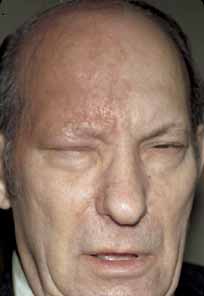

such cases.16 It is important to remember, however, that the eye may be seriously affected

in half of all cases, even if Hutchinson's sign is absent (Fig. 4). Thus, Hutchinson's sign is not entirely reliable as a predictor

of ocular involvement; however, if present, ocular inflammation

is more likely to occur.  Fig. 4 Severe eruption of herpes zoster ophthalmicus with cutaneous necrosis and

sloughing. Involvement of the upper lid and sparing of the lower lid

is evident. Fig. 4 Severe eruption of herpes zoster ophthalmicus with cutaneous necrosis and

sloughing. Involvement of the upper lid and sparing of the lower lid

is evident.

|

HZO begins with a prodrome of severe burning or lancinating pain, dysesthesia

or hyperesthesia over the affected dermatome, mild fever, nausea, and

malaise (Fig. 5). The preeruptive pain may be insidious. At this stage, the cerebrospinal

fluid shows a mild lymphocytic pleocytosis. A cutaneous eruption

usually appears over one dermatomal area 3 to 5 days after the onset

of pain (Figs. 6 and 7). The erythema and swelling may be mistaken for an insect bite or

cellulitis. Initially, the HZO eruption is erythematous and maculopapular, but

soon becomes vesiculopapular, ulcerative, and eventually cicatrizing. Material

in the vesiculopapular eruption is at first clear, but

becomes yellow-brown and purulent as the vesicles erupt and

crust. Because VZV involves the dermis, cutaneous scarring, sloughing, and

subsequent exposure and superinfection can occur (Figs. 8 and 9). Herpes zoster without cutaneous eruption, called zoster sine herpete or zoster sine eruptione, has been observed. Schwab61 reported 16 patients with zoster sine herpete, in whom an anterior uveitis or iridocyclitis was present without ipsilateral